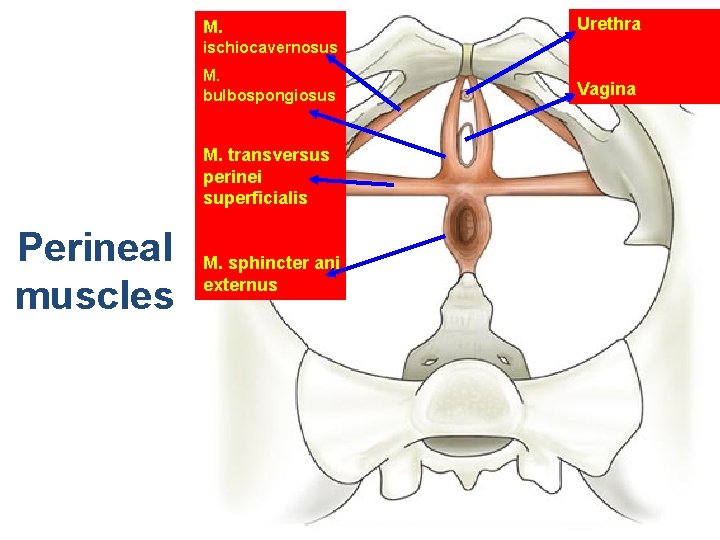

• Sphincter urethrae externus • Bulbospongiosus • Ischiocavernosus • Transversus perinei profundus • Transversus perinei superficialis

M. Urethra ischiocavernosus M. bulbospongiosus M. transversus perinei superficialis Perineal muscles M. sphincter ani externus Vagina

• Ürogenital trigon: – – M. Transversus perinei superficialis M. İschiocavernosus M. Bulbocavernosus M. Transversus perinei profundus • Anal trigon: – M. Levator ani – M. Sphincter ani externus